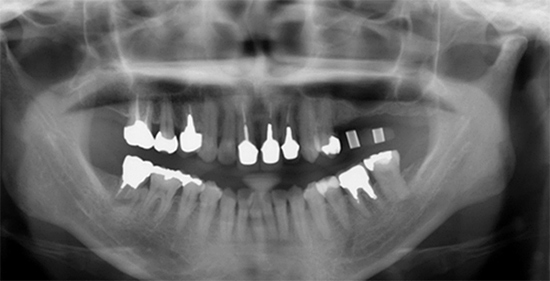

Before

抜歯と同時にインプラント埋入、無切開で行く予定で、抜歯の部位とドリルを合わせています。